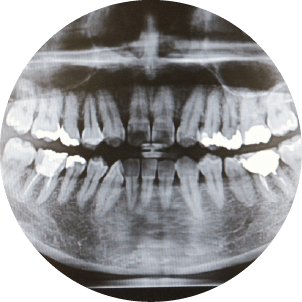

カウンセリングの後、歯や歯ぐきの状態を詳しく確認するために、口腔内検査やレントゲン撮影を行います。レントゲンを使うことで、目に見えない部分や歯の内部まで詳しく確認でき、正確な診断が可能です。